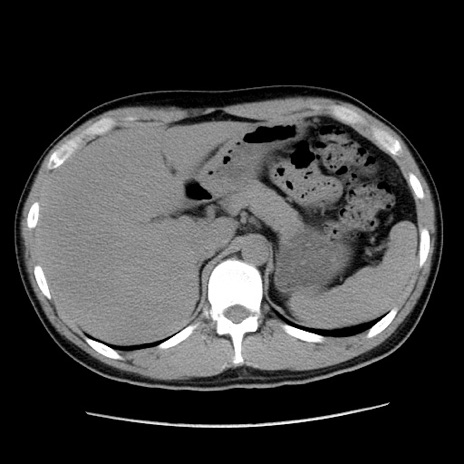

症例36(横断像)

【症例】20歳代 男性

【主訴】心窩部痛

【現病歴】今朝より上腹部痛あり。一旦軽快していたが再度出現したため救急要請。昨日夕に白身の魚を含む刺身を食べた。

【身体所見】BP 136/89mmHg、HR 74/min、BT 37.0℃、腹部:膨満、軟、心窩部に圧痛あり。反跳痛なし、筋性防御なし、腸雑音やや亢進あり。

【データ】WBC 17700、CRP 0.48